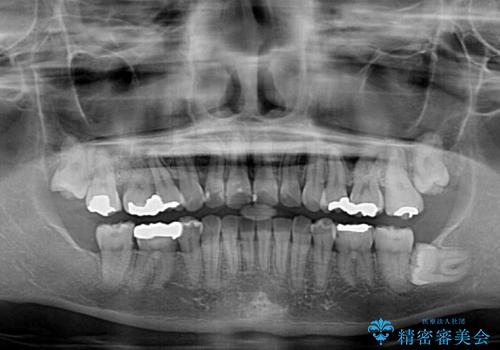

- 上の前歯の出っ歯とでこぼこの歯並びを気にして来院された患者様です。

上下顎歯列ともに前方に突出していましたが、上顎歯列がより前方位にあったため、上顎左右は第1小臼歯を、下顎左右は第二小臼歯を抜歯することとしました。

下顎は過剰歯が埋伏しており、それが原因となってスペースが閉じなかったため、途中で抜歯して速やかに仕上げました。